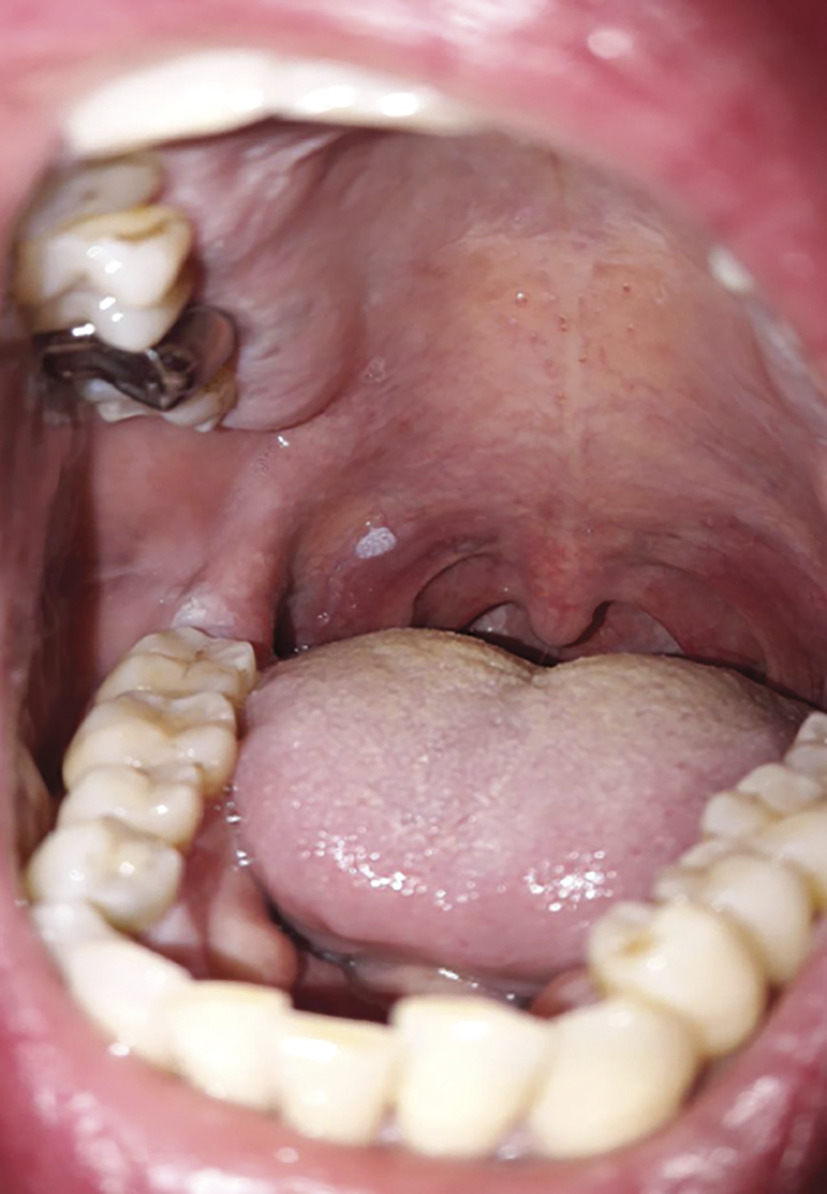

Monique, 45 ans, consulte pour une lésion buccale du voile du palais mou, asymptomatique, qui évolue depuis 1 an (figure). Blanchâtre, d’aspect framboisé, elle n’est ni ulcérée ni douloureuse (flèche). Après exérèse chirurgicale, l’analyse anatomopathologique révèle un papillome verruqueux et l’absence de cellule maligne (exérèse complète).

Cette lésion de la cavité buccale est une végétation généralement unique, non douloureuse, exophytique et de taille modeste. La prolifération lui donne un aspect framboisé avec un reflet blanchâtre fréquent, témoin d’une kératose superficielle. Ces papillomes sont souvent plus petits et plus kératinisés que les condylomes acuminés (buccaux, ils sont rares). Ils siègent volontiers au niveau de la langue ou du palais comme chez cette patiente.